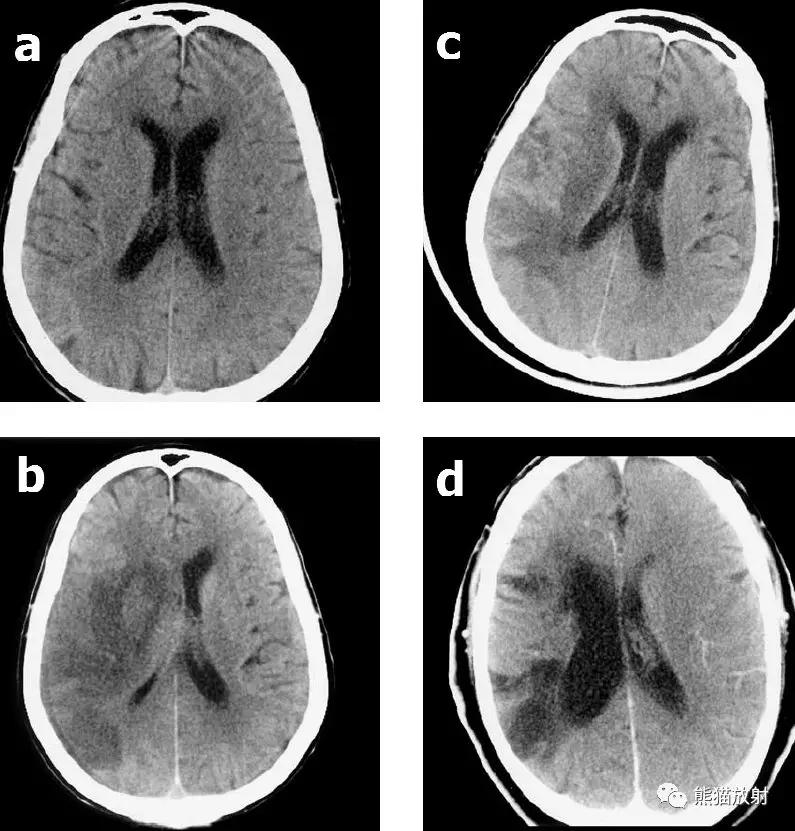

右侧大脑中动脉区域梗死的典型演变:

a)急性期

b)早期亚急性期(2天,从临床起病开始)

c)亚急性晚期(2周后)

d)慢性期(一年后)